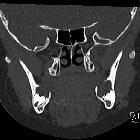

developmental and genetic origin affecting the paediatric craniofacial skeleton. Typical manifestations of nevoid basal cell carcinoma syndrome (NBCCS) in a 16-year-old boy. a Orthopantomography (OPT) shows cystic lesions of the mandible and maxilla (arrows), with unilocular and multilocular pattern and smooth or scalloped borders associated with displaced and unerupted permanent teeth. b Coronal CT scan (bone window) shows ectopic calcifications of the falx cerebri and tentorium cerebelli (arrows) and spotted meningeal calcifications (arrowheads). Brain MRI reveals a cavum veli interpositi on axial T2 (asterisk in c) and coronal contrast-enhanced T1 (asterisk in d) and also vermian dysgenesis (arrowheads in d)